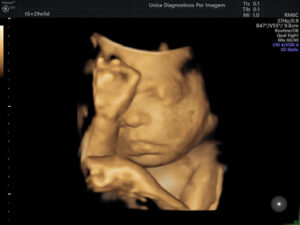

Exame importante que tem como objetivo avaliar a anatomia do feto e detectar possíveis malformações. Deve ser realizado preferencialmente realizado